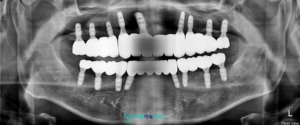

식립 이후에는 임플란트와

잇몸뼈가 결합되는 과정을 충분히 거친 뒤,

상태를 확인하고 최종 보철물 제작을 위한

인상채득을 진행하였습니다.

최종 보철물은 자연치아와

유사한 특성을 가진 지르코니아를 활용해

마무리하였습니다.

모든 치료가 마무리된 후의

파노라마 사진과 구강 내 모습입니다.